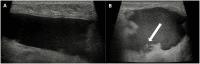

The surgical procedure of AFT and follow-up with imaging modalities including mammography (MG), ultrasound (US), and MRI in patients with a total breast reconstruction with AFT are summarized to illustrate the radiological normal and suspicious findings for malignancy.

Imaging after a total breast reconstruction with AFT appears to be based mostly on benign imaging findings with an overall low biopsy rate. As higher volumes are injected in this technique, the risk for the onset of fat necrosis increases. Imaging findings most often are related to fat necrosis after AFT. On MG, fat necrosis can mostly be seen as oil cysts. The occurrence of a breast seroma after total breast reconstruction with AFT is an unfavourable outcome and may require special treatment. Fat deposition in the pectoral muscle is a previously unknown, but benign entity. Although fat necrosis is a benign entity, it can mimic breast cancer (recurrence).